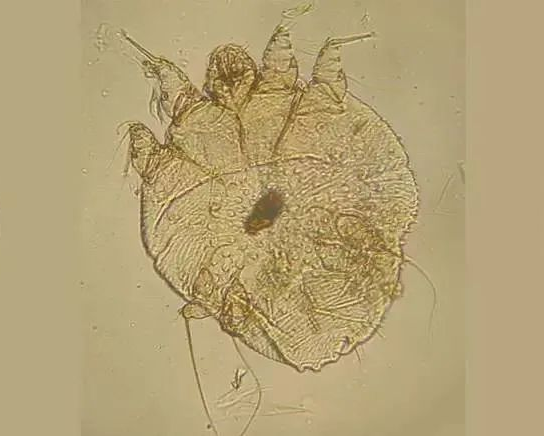

疥螨,图片来源维基共享资源

床是螨虫最容易滋生的地方。螨虫引起的皮炎多为水肿性风团样丘疹、丘疱疹或瘀斑,其上有小水疱,常伴抓痕和结痂。